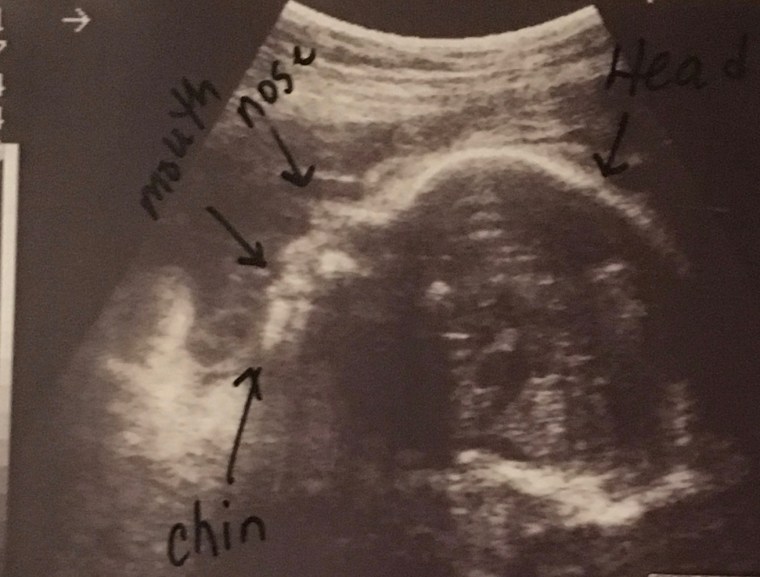

The third Sunday in January, our pastor affirmed the sanctity of the tiniest lives, the unborn people being knit together in their mothers’ wombs and the next day my mailbox sat empty, the stock market went quiet and public offices closed their doors to commemorate the sacrifice of MLK Jr. and the dignity of all the black skinned image bearers of our Creator who share the same inalienable rights as every other epidermal variation. Truth is, each person representing every race, age, demographic and sexual orientation is stamped by God as innately valuable and deeply loved.